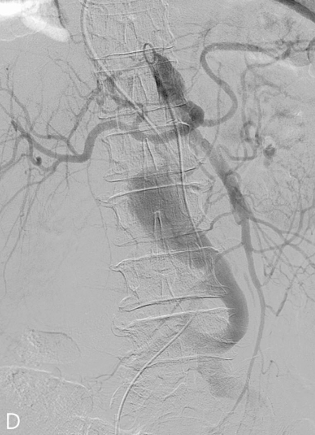

Fig 2D

(D) Angiogram of the true lumen via femoral access showed the luminal narrowing of true lumen at infrarenal level and mesenteric arteries were arising from true lumen.